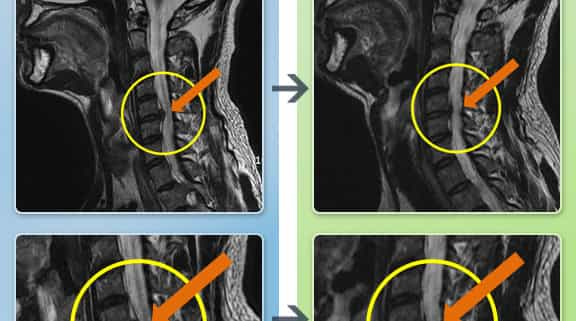

Before and After Neck Pain MRI